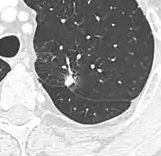

- A lung nodule abutting a pulmonary cyst is a rare finding, yet indicating cancer.[9]

- Bubble-like lucencies in the nodule indicate cancer:[9]

- Vascular convergence is where vessels converge to a nodule without adjoining or contacting the edge of the nodule, and is mainly seen in peripheral subsolid lung cancers.[9] It reflects angiogenesis.[9]